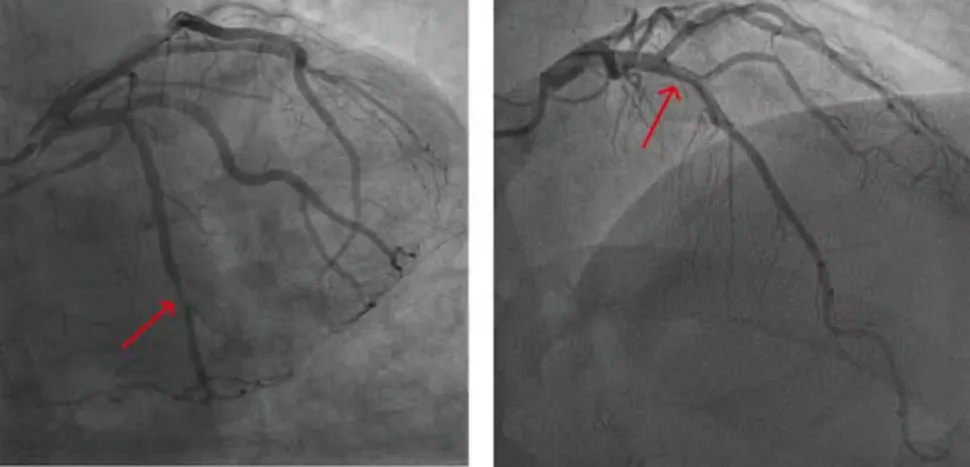

女性比男性更有可能患心血管疾病,表现为多条未完全“堵塞”的狭窄动脉,导致胸痛,因为血流无法增加到足以满足运动时更高的氧气需求,就像低流量淋浴头一样。当胸痛以这种方式出现时,医生称这种情况为缺血,没有阻塞性冠状动脉。相比之下,男性更有可能在可以用支架或心脏搭桥手术打开的集中区域出现“堵塞”动脉。多条狭窄动脉的治疗方案落后于典型“阻塞”动脉的治疗选择,这使女性处于不利地位。

血管不需要被斑块堵塞而导致心脏病。(图片来源:uux.cn赵和龚2023/数学生物科学与工程,CC BY 4.0)